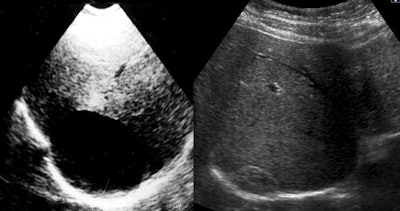

Diagnosis and classification of liver CE is based mainly on ultrasound, which is easy to use and allows visualization inside the cystic cavity to determine the contents and, thus, the subtype of cyst, he explained. After ultrasound, MRI and MR cholangiopancreatography (MRCP) are useful when communication between the cystic cavity and the biliary system is suspected. CT is less sensitive for demonstrating cyst content, but can be useful in defining the exact location of the cyst in the abdomen or liver if indicated, usually because the doctor suspects some kind of dissemination in the abdomen or thorax.

Ultrasound shows a liver CE 1 on the right side before the procedure in 1991 and a solid remnant with "pseudotumor appearance" -- 23 years after treatment. Images courtesy of Dr. Okan Akhan.Following on from their experimental study in sheep using a catheterization technique with hypertonic saline and alcohol, the Ankara group worked on a nonsurgical modified catheterization technique (MoCaT) based on complete evacuation of all cyst content, including the generated membrane and daughter vesicles, namely the fluid and the solid parts of the cyst. MoCaT, first described in 2007, has generated good results and low recurrence rates.